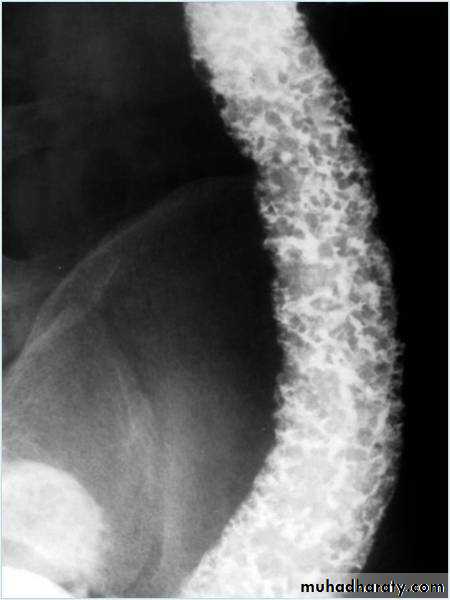

Barium enema showed: dilated large bowel ,with absent haustration and multiple filling defects; Pseudopolyps.